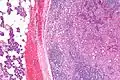

Intermed. mag.

Very high mag.

Basophilic, bland cells similar to acinar cells. Growth pattern: solid - acinar cells, microcytic - small cystic spaces mucinous or eosinophilic, papillary-cystic - large cystic lined by epithelium, follicular - similar to thyroid tissue.

These tumors, which resemble serous acinar cells, vary in their behavior from locally aggressive to blatantly malignant.